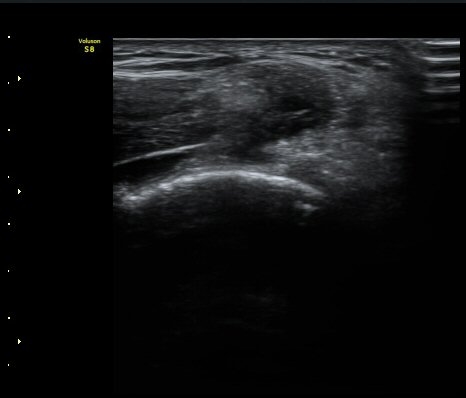

¼Ò½Ç ¹× Àü¹ÝÀûÀÎ Àú¿¡ÄÚ ºÎÁ¾ÀÌ °üÂûµÈ´Ù(±×¸² 1, 2, 3). ±¼°î°Ç ÀϺδ Á¤»óÀûÀÎ °í¿¡ÄÚ

¼¶À¯ ¾ç»óÀ¸·Î °üÂûµÈ´Ù(±×¸² 4). ÈûÁ٠Ⱦ´Ü¸é °Ë»ç¿¡¼­µµ °Ç³» ¿¬°á¼º ¼Ò½Ç°ú Àú¿¡ÄÚ